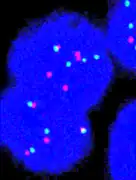

Fluorescence in situ hybridisation

FISH can be used to measure the number of copies of the gene which are present and is thought to be more reliable than immunohistochemistry.[45] It usually uses chromosome enumeration probe 17 (CEP17) to count the amount of chromosomes. Hence, the HER2/CEP17 ratio reflects any amplification of HER2 as compared to the number of chromosomes. The signals of 20 cells are usually counted.

Algorithm for the evaluation of HER2 on fluorescence in situ hybridization (FISH).[46]